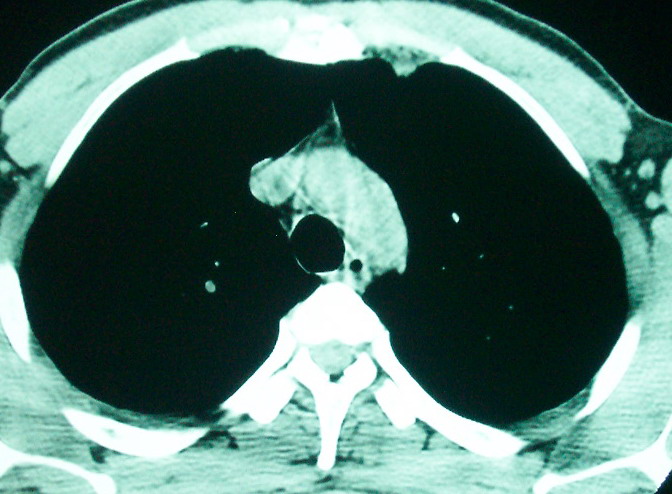

m      37y      发热   咳脓痰月余      ct肺脓肿但住院抗炎治疗后双肺内结节不知该如何解释

治疗后见左肺下野病灶较前缩小但双肺内结节影似无变化请较各位老师该如何下结论    治疗前wbc14.5 治疗后wbc 11.0

空洞内可见小结节样密度影考虑合并真菌感染

左下肺病灶除了明显的厚壁空洞 气液平外,明显见壁结节,另两肺多发小结节,综合考虑:左下肺周围性肺癌伴肺内转移.

鳞癌肺肺转移:厚壁空洞,洞壁厚薄不均,内似有壁结节,肺脓肿临床有无提示,血像如何?病灶周围很干净,没有明显渗出,很勉强?

如果你仔细的同层面对比,你会发现所有的病灶均有比较明显的吸收、缩小。病变的形态,特别是脓肿的形态、壁的厚薄、内壁均有很大的变化,均在往好的方面发展。与临床症状、血像均符合,治疗效果比较显著,就是肺脓肿并双肺的化脓性炎症灶。